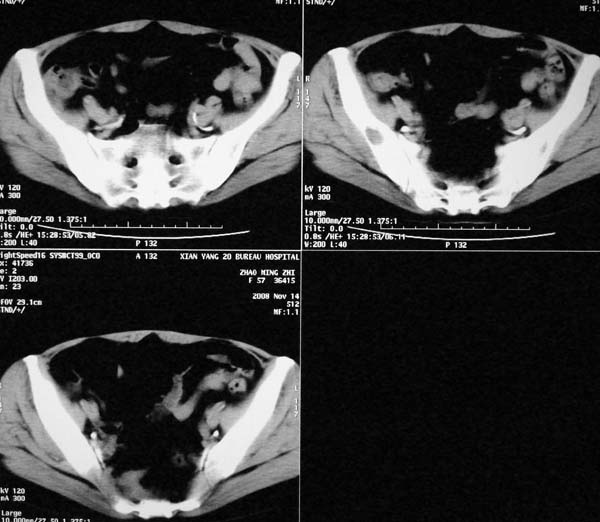

以下是引用dr.yang在2008-11-9 21:56:00的发言:[br]右肾上极占位?建议增强

以下是引用x-man在2008-11-9 22:30:00的发言:[br]建议先增强,右肾影明显增大,上极见边不清低密度肿块影,肿瘤待定.

以下是引用卜一在2008-11-10 8:09:00的发言:[br]建议先增强,右肾影明显增大,上极见边不清低密度肿块影,肿瘤待定.支持!另:第一次碎石是否肾受到损伤?合并感染?不知第一次碎石前是否做过彩超?

以下是引用dsl555在2008-11-9 23:57:00的发言:[br]建议先增强,右肾影明显增大,上极见边不清低密度肿块影,肿瘤待定. [br] [br]